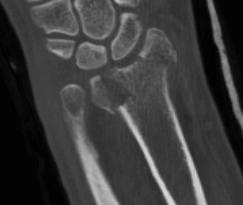

Distal Radius Fracture Articular Step Coronal CTDistal Radius Fracture Articular Step Sagittal CT

Articular incongruency > 2 mm

Distal Radius Fracture DRUJ incongruentDRUJ FractureDRUJ Fracture CT

Sigmoid notch disruption and DRUJ instability